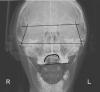

Skip Опубликовано 31 января, 2010 Поделиться Опубликовано 31 января, 2010 И что дает вам томография?Визуализацию и анализ взаимного соотношения скелетных черепных структур, а также шейного отдела позвоночника.., скучно вообщем... Ссылка на комментарий

Skip Опубликовано 1 февраля, 2010 Поделиться Опубликовано 1 февраля, 2010 Вы просто представьте внешний вид лица человека в профиль у которого кривая Шпее имеет обратный наклон.Это примат получается. В ранних стадиях эволюции. Такое бывает когда с лицевой дугой не очень правильно обращаются или гипсуют модель извращенными методами. Или совсем без первого и второго. PS. Я понимаю,когда Шпее параллельна верхней раме артикулятора.... Но чтоб так...Всё будет именно так выглядеть, если регистрация и монтаж проводились в плоскости Кампера, т.е. наиболее близкой к истинно горизонтальной плоскости... HIP-плоскость, в которой я монтирую, тоже покажет такую картину( сюда же Fox plane, Kois Analyser). Кстати, профили гомосапиенс выглядят вполне презентабельными... В некоторых узких кругах, этот феномен называют Pitch down, его также можно видеть на боковой ТРГ, что подтверждается несложным анализом... Соответственно, передне-задняя окклюзионная кривая (Шпее) будет с реверсом... З.Ы. В шейном отделе всё скомпенсируется... Ссылка на комментарий